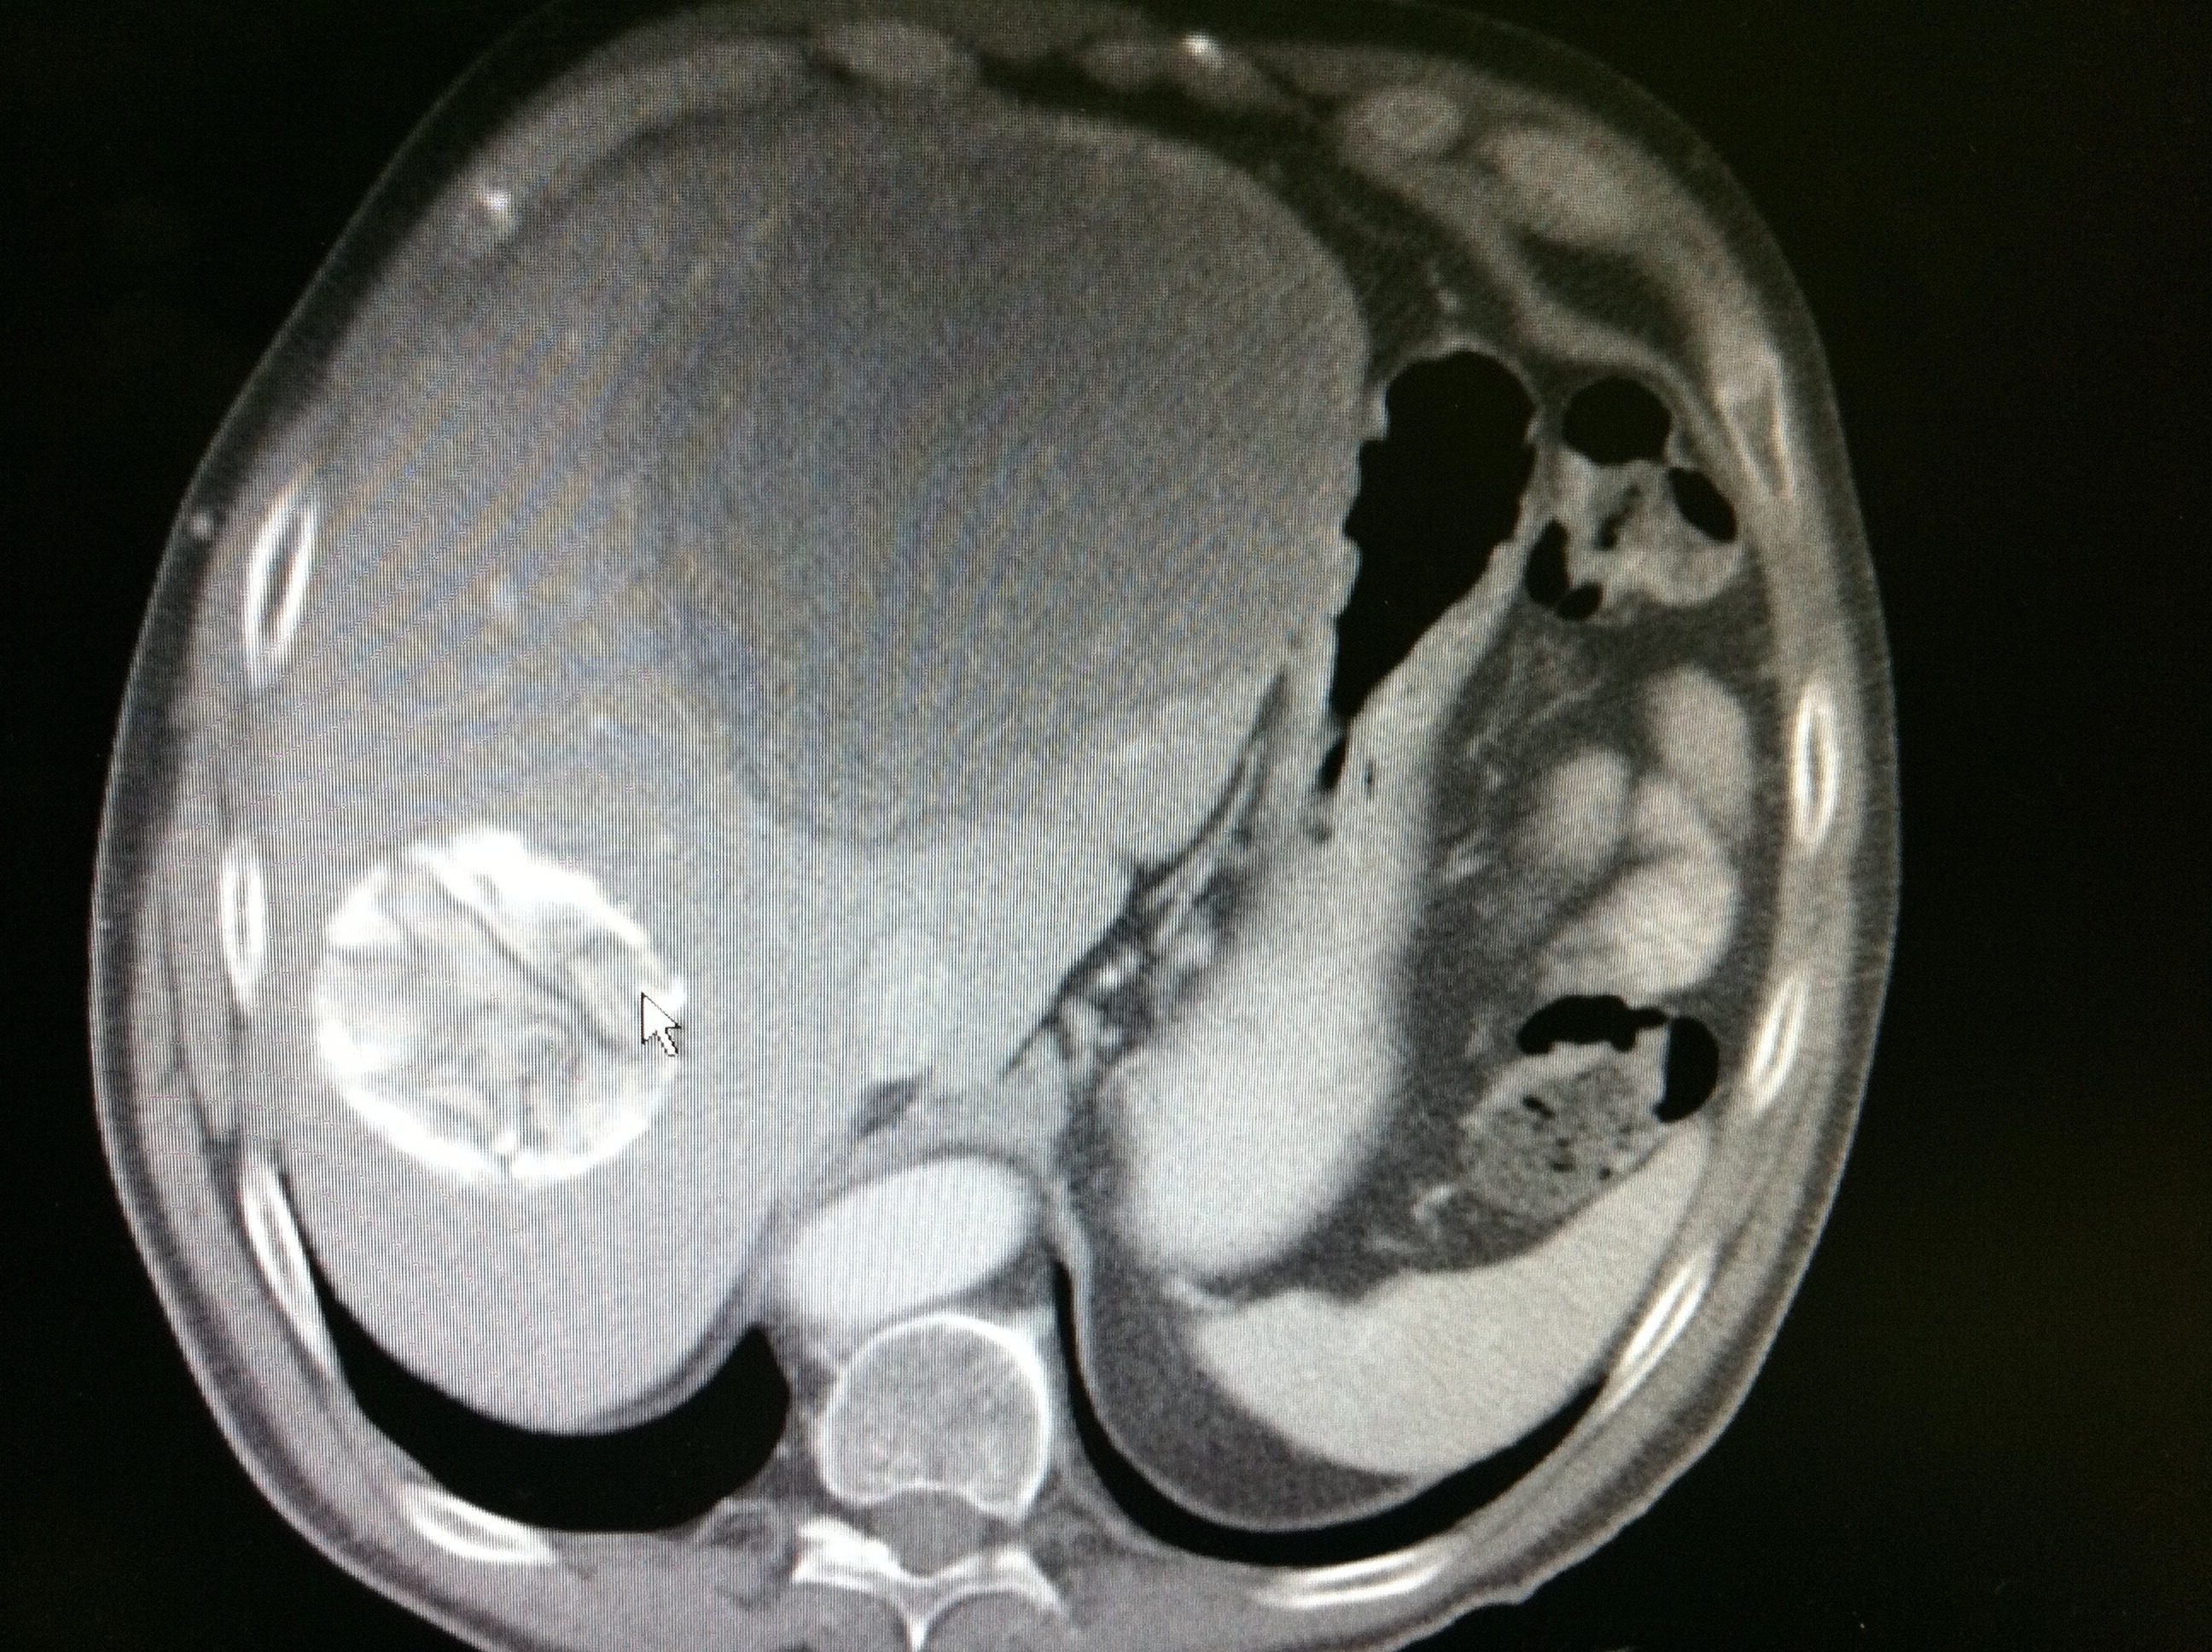

A 47-year-old male farmer from China with a history of chronic Hepatitis B (not on treatment) and biliary stricture in the past presented with complaints of fever, sharp epigastric abdominal pain and nausea/ bilious vomiting that began 48-72 hours prior to admission. Liver function tests were mildly elevated. He was here visiting his daughter from China and was in the U.S for the past 2 weeks. Of note, he had lost about 10 lbs. in the last 5-6 months; this was non-purposeful in nature. ERCP was performed given his symptoms and lab findings, with placement of a stent in the biliary tree due to the presence of another stricture that was found; however, CT scan of the abdomen/pelvis with contrast performed just prior to the ERCP revealed the findings below.

What do you think these findings best represent?

- Hepatocellular carcinoma

- Entamoeba liver cyst

- Echinococcus liver cyst

- Tuberculosis

- Q-fever infection

- Fasciola hepatica infection